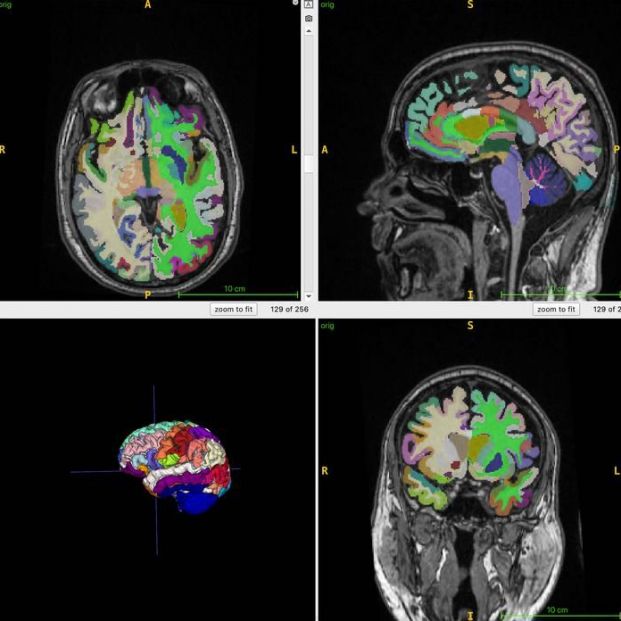

Imágenes cerebrales del estudio. (Cyrus Raji y RSNA)

“Los participantes con más músculo tendían a tener cerebros de aspecto más joven, mientras que aquellos con más grasa abdominal oculta en relación con su músculo tenían cerebros de aspecto más envejecido. La grasa subcutánea no se relacionó con el envejecimiento cerebral. En resumen, más músculo y una menor proporción de grasa visceral/músculo se relacionaron con un cerebro más joven”, ha insistido el Dr. Raji.